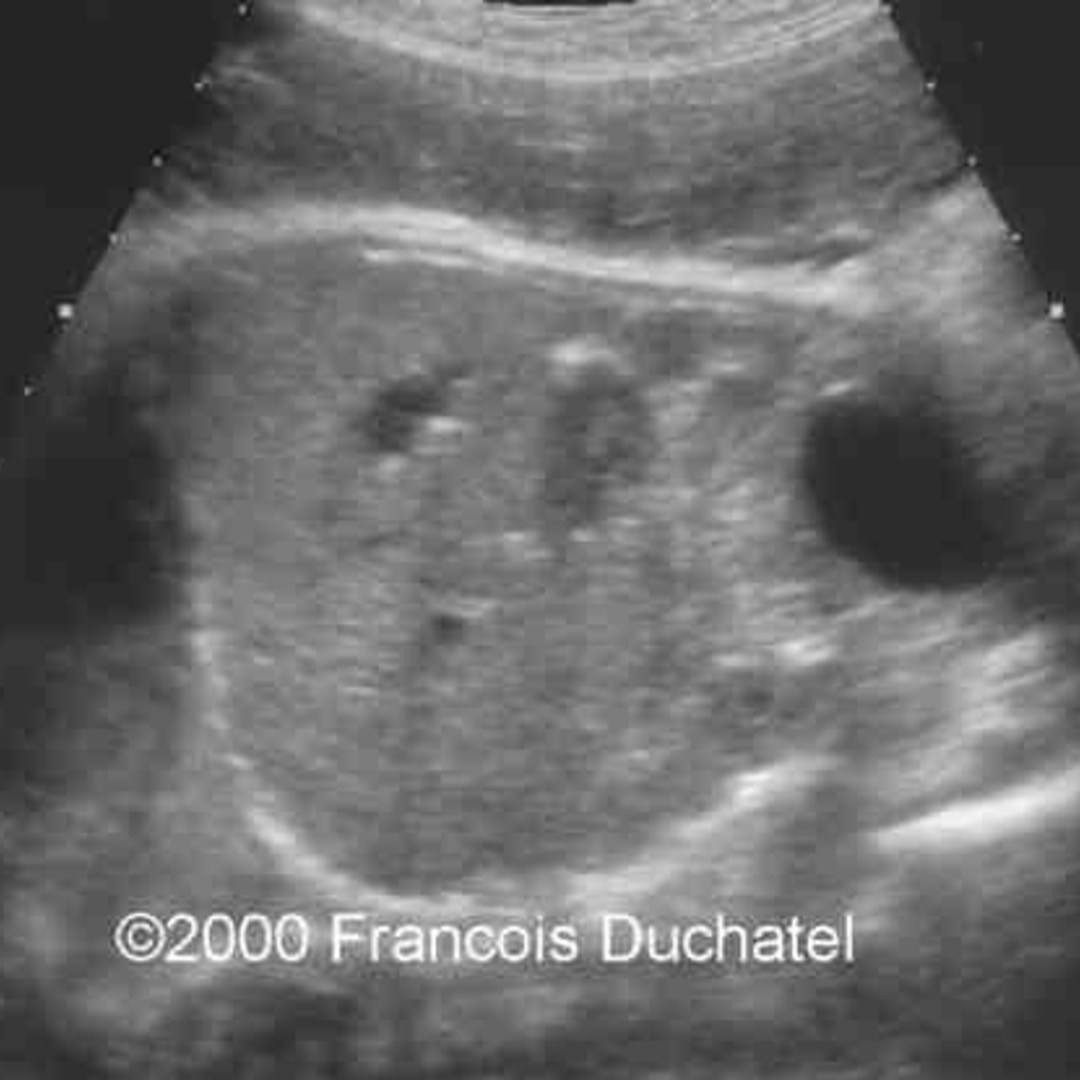

From www.youtube.com

ultrasound video showing hepatic calcification YouTube How To Cure Liver Calcification Recognition of the spectrum of hepatic. They can affect various parts of. if the symptoms have started to present, and the calcified nodules are larger and caused due an underlying infection that has started to affect regular. calcifications are hard nodules that form when calcium builds up in soft tissues. liver calcifications may be seen in a. How To Cure Liver Calcification.